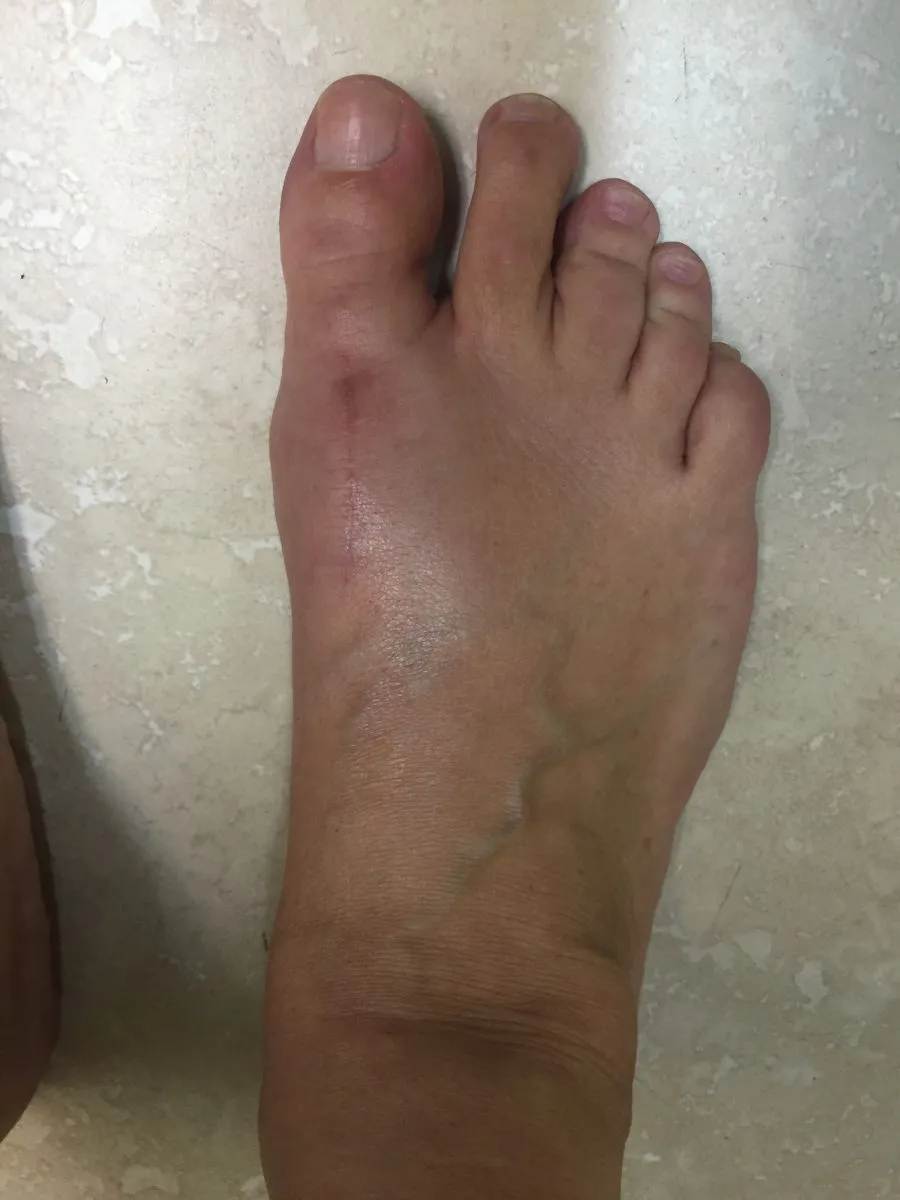

Intraop Pic Immediately After Correction

3 Days Postop

During surgical correction of the bunion a v-shape bone is made in most cases to translate the head of the 1st metatarsal laterally which creates an overhang of bone from the previous position of the bone (pictured left). The overhang is remove and the new position of the bone is held with some type of fixation which varies from screws, staples, or pins which is the case here. The pin is buried left in permanently (pictured right).